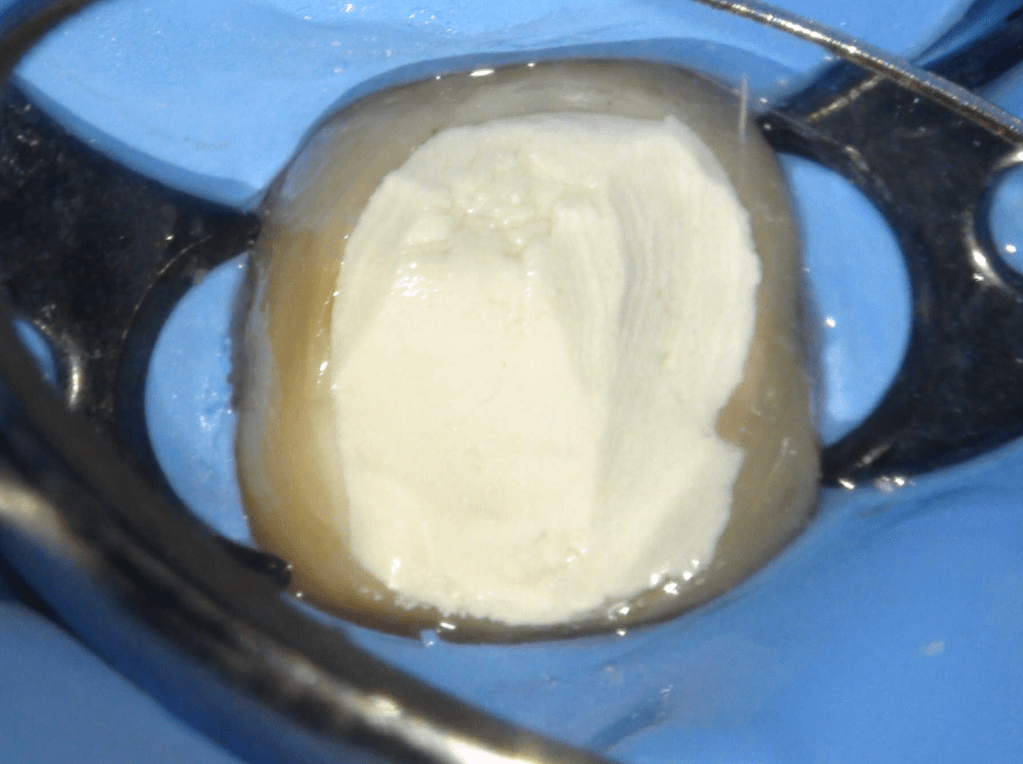

Pulpotomía biodentine + reco preendio